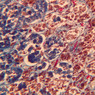

The zona glomerulosa is located immediately beneath the capsule (B-60 adrenal gland, dog [10x, 20x] [20x, 40x]; B-59 [2.5x, 10x, 20x] [2.5x, 10x, 20x]). Its constituent cells are arranged in arcs or spheres, and, owing to their relatively small size, their nuclei appear to be close together. Cells of the zona glomerulosa secrete mineralocorticoids (e.g., aldosterone). The zona fasciculata consists of parallel columns or cords of cells that radiate toward the medulla and are separated by blood sinusoids (B-60 [2.5x, 10x, 20x, 40x]; B-62 [20x, 40x]). Owing to the extraction of lipids during histological processing, the cytoplasm of cells in the zona fasciculata appears highly vacuolated or "foamy". Cells of the zona fasciculata secrete glucocorticoids (e.g., hydrocortisone & cortisone) and some gonadocorticoids (weak androgens). The zona reticularis is the deepest cortical layer and lies adjacent to the medulla (B-60 [20x, 40x]; B-62 [20x, 40x]). It is characterized by irregular, interconnecting cords of cells which are separated by anastomosing capillary networks or sinusoids. Cells of the zona reticularis, which are smaller than those of zona fasciculata and do not contain as many lipid vacuoles, secrete gonadocorticoids and some glucocorticoids.

The medulla is composed of large epithelioid cells, arranged in small groups or cords which are separated by blood vessels. Usually, several large veins mark the center of the medulla. When fresh adrenal gland is incubated in solutions of chromium salts (as was the specimen on slide B-61), brownish precipitates form in the cells of the medulla-- hence, the name chromaffin cell (B-61, chromaffin [2.5x, 10x, 20x, 40x] [2.5x, 10x, 20x, 40x-labeled]). The more darkly stained chromaffin cells are known to contain norepinephrine, the less darkly stained cells, epinephrine. In essence, chromaffin cells are specialized postganglionic sympathetic neurons. How does the ultrastructure of these cells differ from that of the secretory cells of the adrenal cortex?